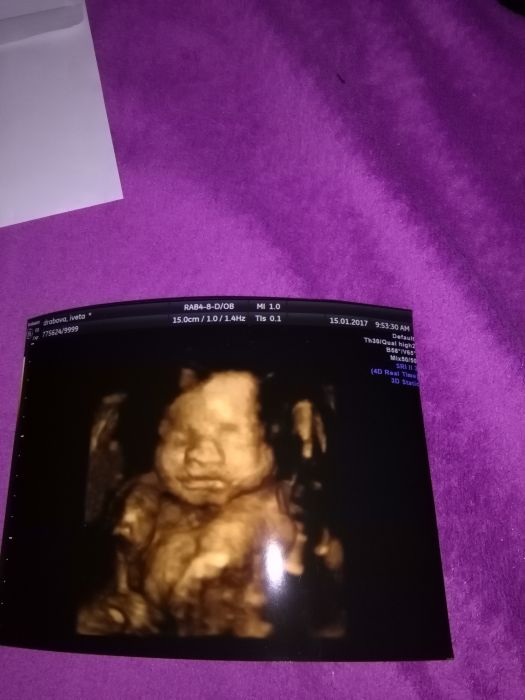

My byli na 4D na zacatku ledna v 25tt a byli jsme nadseni, doktor taky rikal, ze je pekne videt :) Mame video 4D a pak komentovane video 2D. Bude to krasna pamatka.

Jeste teda pridam pupik minuly tyden :)

Ahoj holky. Já jdu na kontrolu ve čtvrtek, tak jsem taky zvědavá jestli už je prcek otočený. Ale tím jak mě pořád šťourá pod pravým žebrem tak si myslím že jo, už je to fakt kolikrát nepříjemný :) Už i vím jaký to je když pálí žáha, vzbudilo mě to v noci. My jsme byli na 3D ve 25.tt a prcek se ukázal hezky :) Cukrovku naštěstí nemám, ale myslím si že těch pár týdnů do konce už by se to dalo i vydržet :) Utíká to jako voda. Přidávám foto pupíku a z toho 3D.